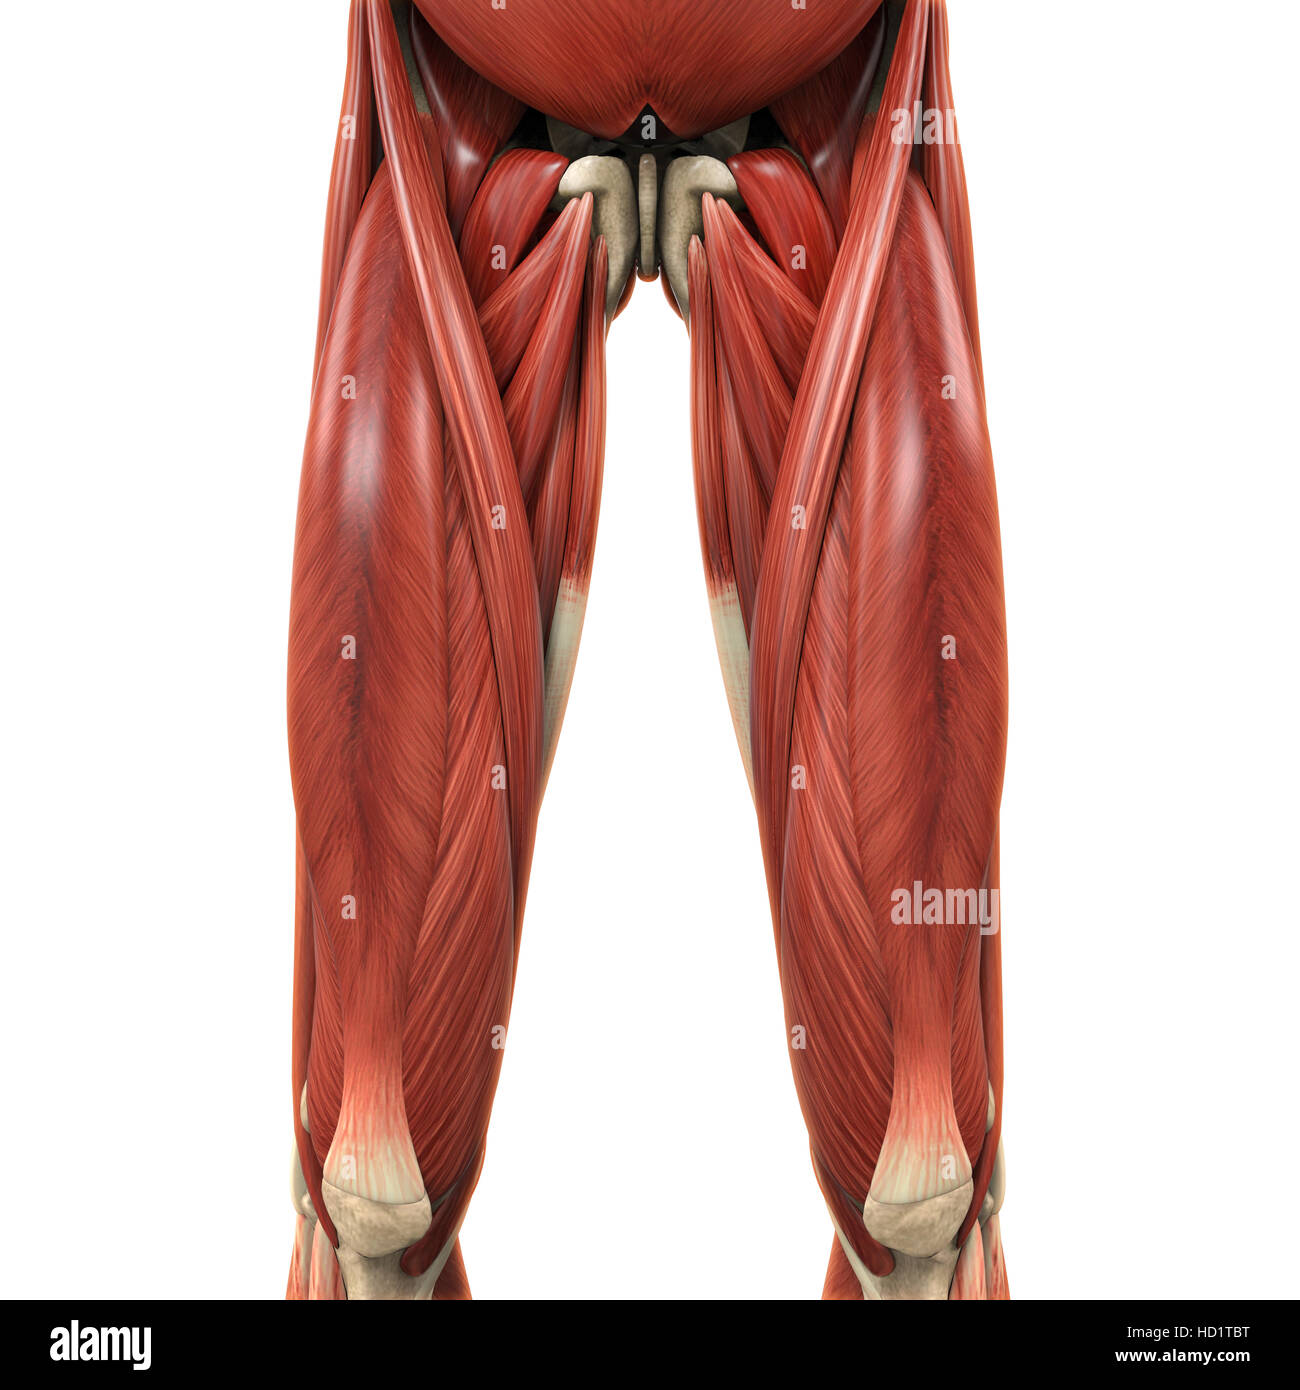

Anatomie des muscles des jambes supérieure Banque D'Imageshttps://www.alamyimages.fr/image-license-details/?v=1https://www.alamyimages.fr/photo-image-anatomie-des-muscles-des-jambes-superieure-128504250.html

Anatomie des muscles des jambes supérieure Banque D'Imageshttps://www.alamyimages.fr/image-license-details/?v=1https://www.alamyimages.fr/photo-image-anatomie-des-muscles-des-jambes-superieure-128504250.htmlRFHD1TDE–Anatomie des muscles des jambes supérieure